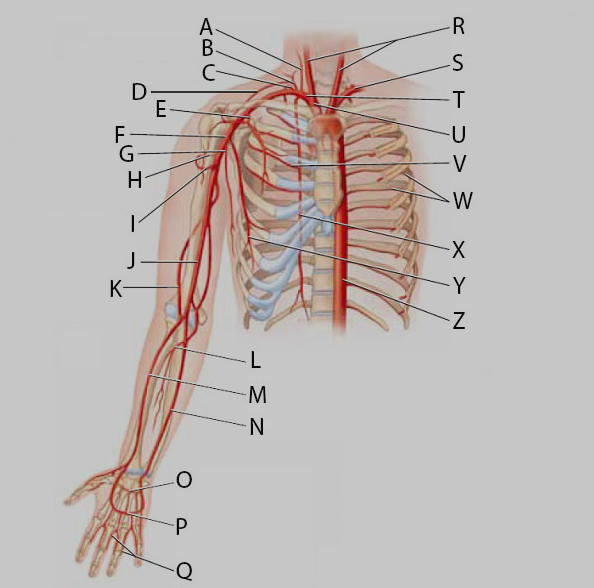

Aortic Arch

Ascending/descending aorta

Axillary artery/vein

Brachial artery

Brachiocephalic artery

Radial artery/vein

Subclavian artery/vein

Thoracic aorta

Abdominal Aorta

Ulnar artery/vein